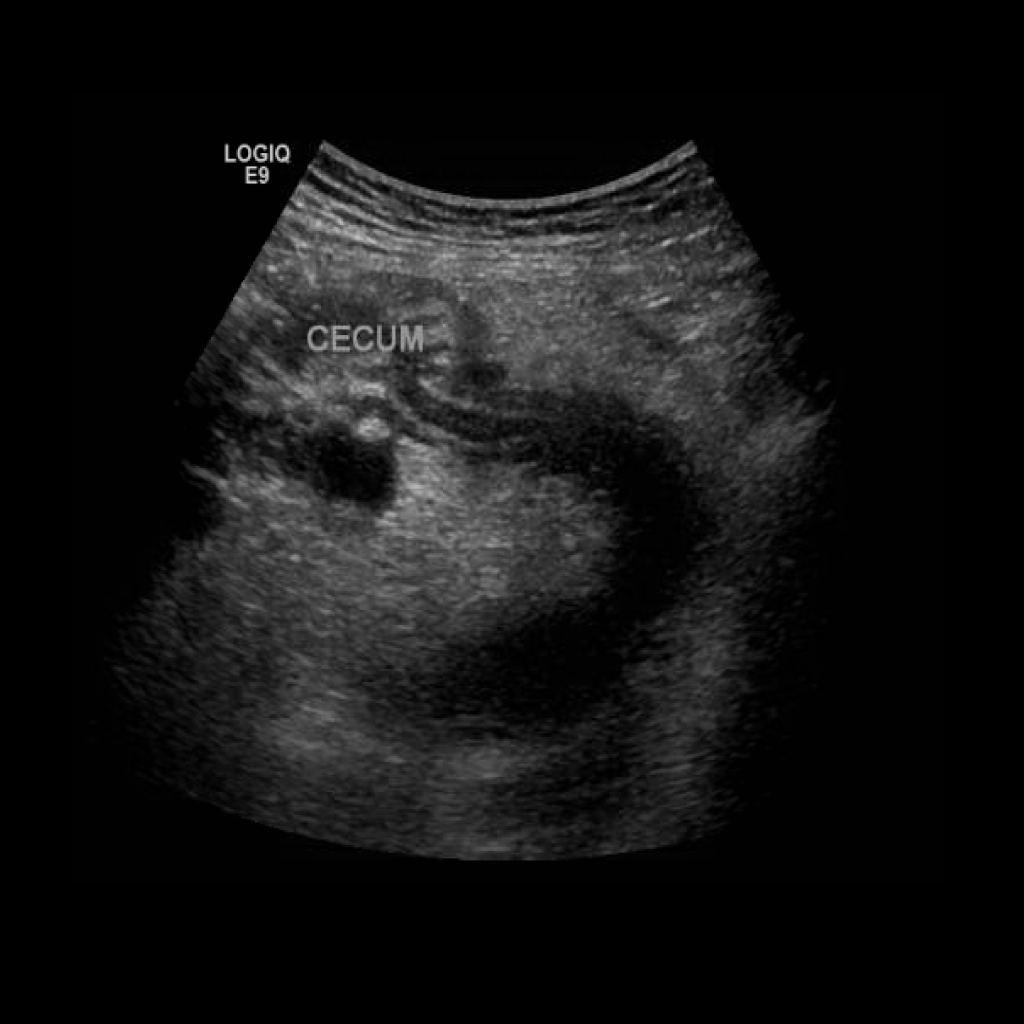

Appendicitis 3

0.9 cm appendicitis curled on itself with, fat stranding trace free fluid.